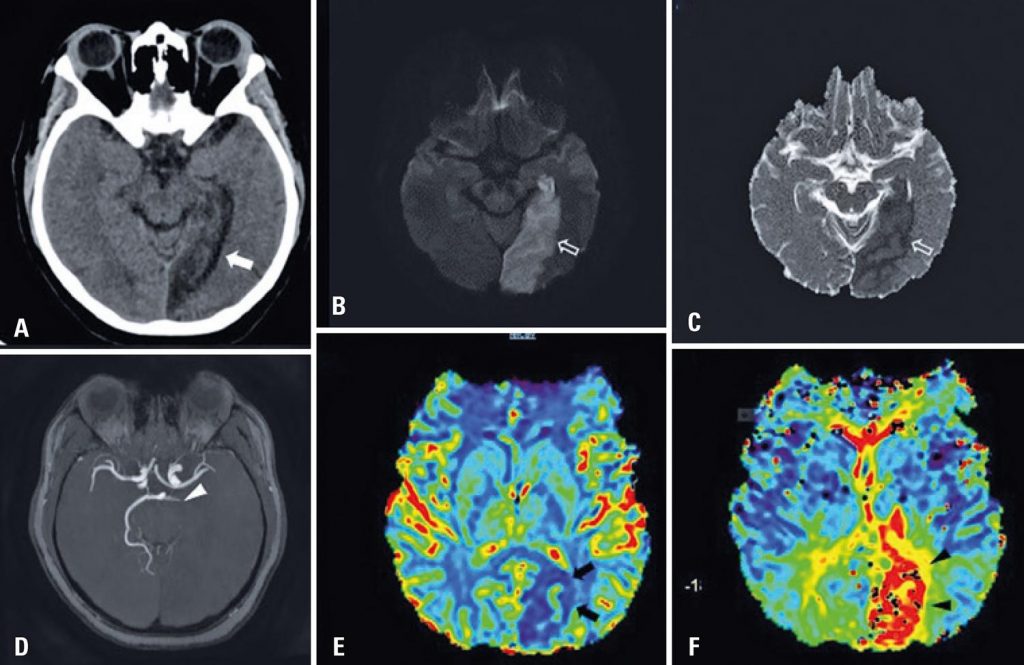

In this sample, the clinical severity of the symptoms varied from mild to critical. Ischemic stroke was observed in four patients, hemorrhagic events occurred in five cases. Three patients evolved with large parenchymal hemorrhage, and one presented petechial bleeding foci. In one case, we observed subarachnoid hemorrhage associated with bilateral hypodensity in both globus pallidus. Typical posterior reversible encephalopathy syndrome findings were observed in one patient on brain computed tomography.